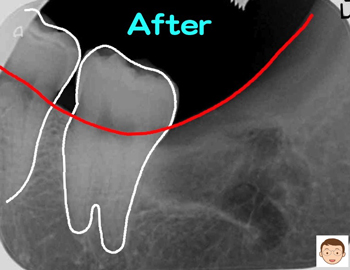

今年一番の難抜歯

コラム「今年一番の難抜歯」の画像